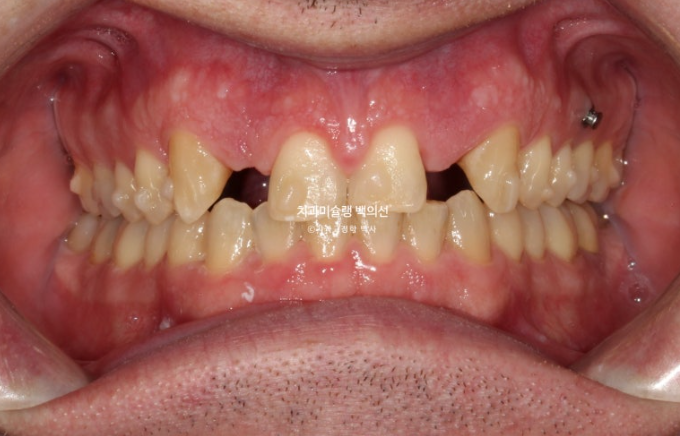

오늘은 부원장님 인비절라인 케이스를 보면서 앞니 2개가 선천적으로 없는 경우 (결손치) 인비절라인 교정 후 임플란트까지 치료 진행과정에 대해 보여드리겠습니다.

24년 1월 교정치료를 위해 내원한 외국인 환자분입니다.

23.01

위 앞니 4개중 2개가 없습니다. 앞니가 크게 벌어져 있고 아래 앞니가 위로 솟아 위 입천장 잇몸을 칠 정도의 심한 과개교합이 있습니다.